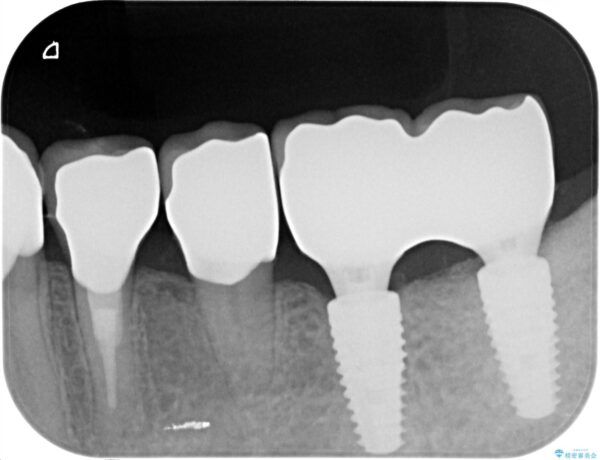

治療前

劣化の進んだブリッジの再治療[ 不適合な補綴物による虫歯の再発 ] 治療前画像 劣化の進んだブリッジの再治療[ 不適合な補綴物による虫歯の再発 ] 治療前画像 劣化の進んだブリッジの再治療[ 不適合な補綴物による虫歯の再発 ] 治療前画像

治療中

劣化の進んだブリッジの再治療[ 不適合な補綴物による虫歯の再発 ] 治療中画像 劣化の進んだブリッジの再治療[ 不適合な補綴物による虫歯の再発 ] 治療中画像 劣化の進んだブリッジの再治療[ 不適合な補綴物による虫歯の再発 ] 治療中画像